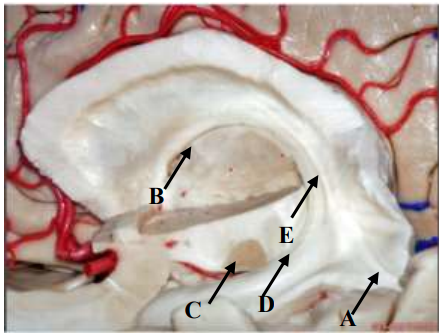

Qual seta aponta para a Fímbria do Fórnix?

Provas